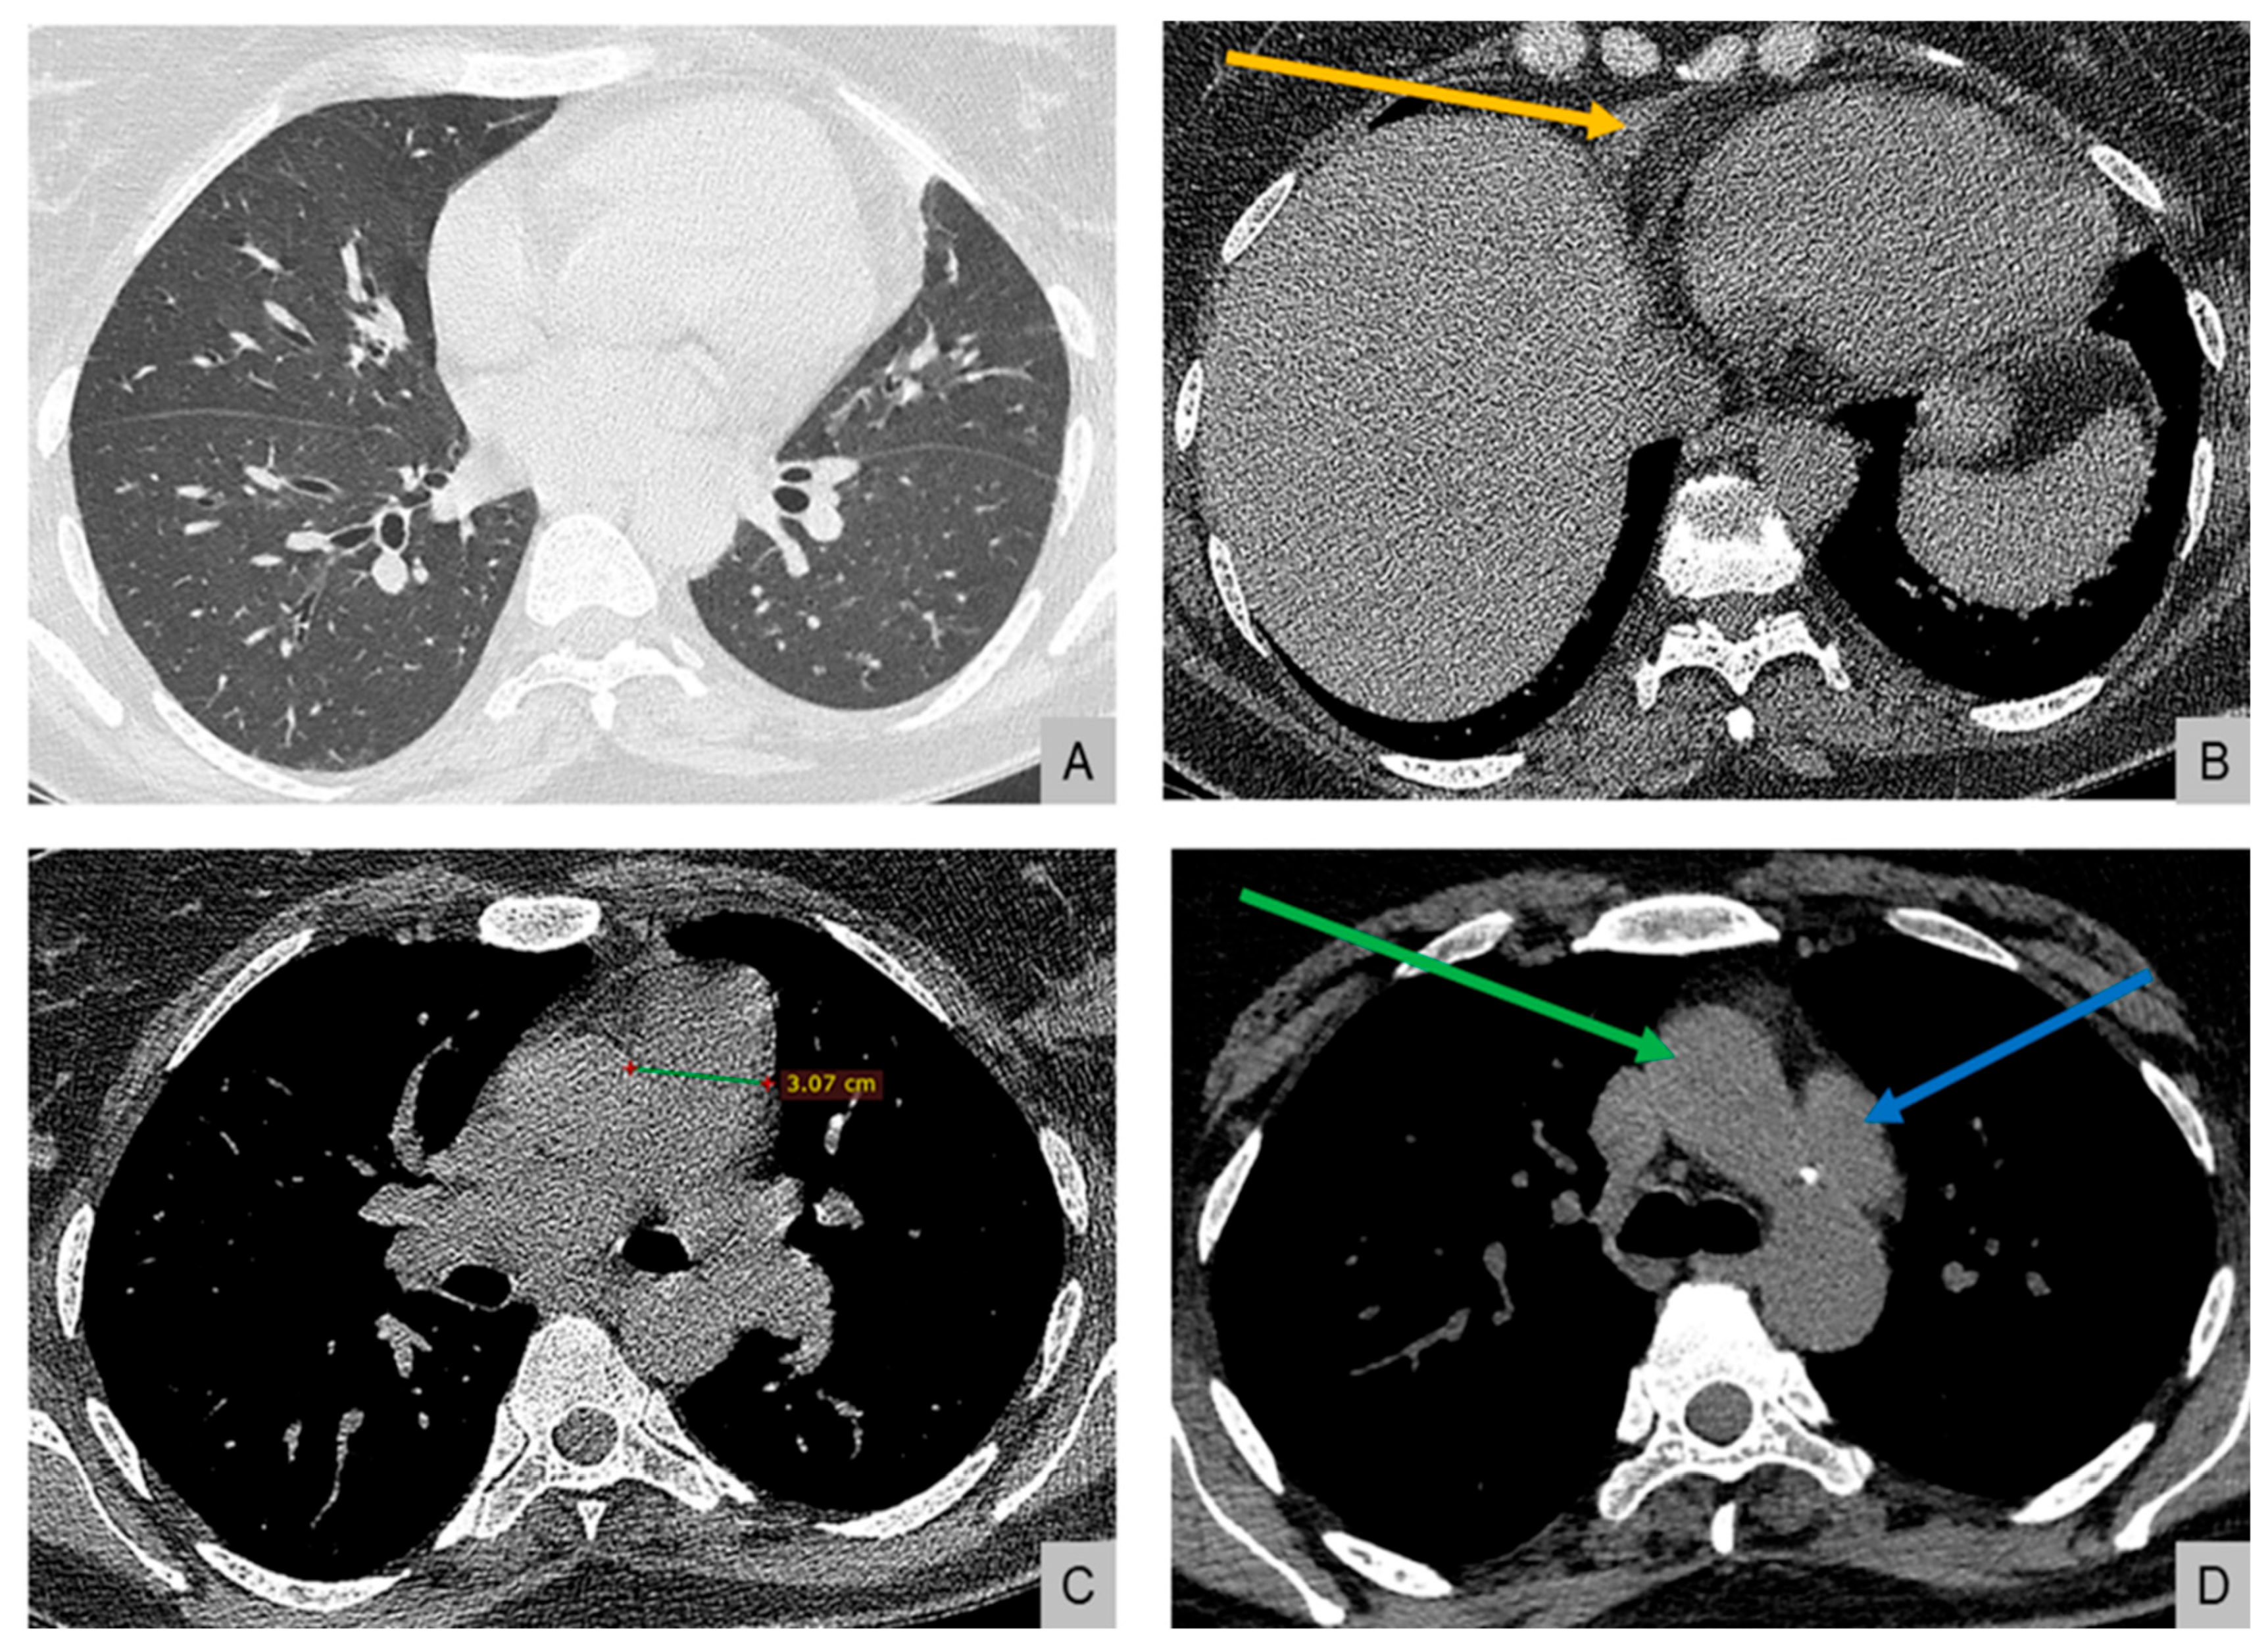

Electrocardiography demonstrated right atrial enlargement and right ventricular strain. Chest radiography (Figure 1) revealed cardiomegaly, pulmonary congestion with enlarged central pulmonary arteries, bilateral pleural effusions, and elevation of both hemidiaphragms.

Figure 1. Chest radiography on admission demonstrating cardiomegaly with dilation of the central pulmonary arteries, increased interstitial markings with a perihilar “bat-wing” pattern, and bilateral pleural effusions, all indicative of pulmonary congestion. Bilateral elevation of the hemidiaphragms is also noted, possibly related to underlying myopathy.